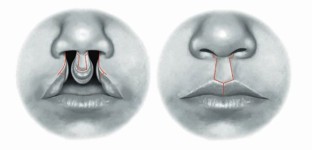

Tajima S, Maruyama M. Reverse-U incision for secondary repair of cleft lip nose. Plast Reconstr Surg 1977; 60: 256-261.

McComb H K, Coghlan B A. Primary repair of the unilateral cleft lip nose: completion of a longitudinal study. Cleft Palate Craniofac J 1996; 33: 23-31.

Fisher D M, Sommerlad B C. Cleft lip, cleft palate, and velopharyngeal insufficiency. Plast Reconstr Surg 2011; DOI: 10.1097/PRS.0b013e3182268e1b.